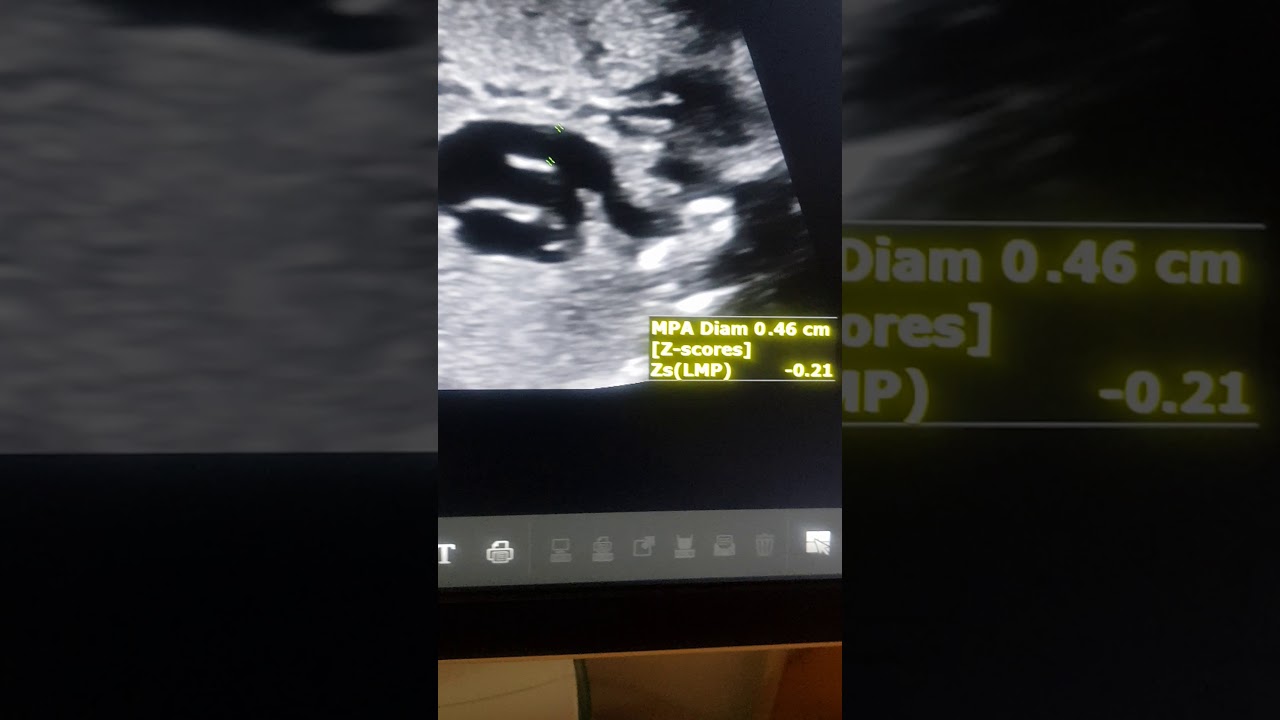

Fetal echo Dr Pradeep Srinivasan REFER SERIES Ductus narrowing in TOF refer.Mediknit.org

Описание: Fetal echo showing malaligned VSD with aortic over ride ectatic aorta slightly small pulmonary artery confluent branch pulmonary arteries and NARROW DUCTUS ARTERIOSUS.Dr Pradeep Srinivasan under REFER SERIES. Refer.mediknit.org